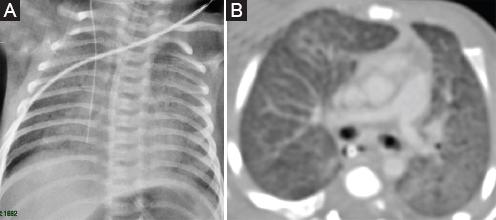

Como la evolución clínica-radiológica fue favorable, el paciente dejó el oxígeno luego del tercer ciclo de pulsos de metilprednisolona. El paciente no requirió atención en la unidad de cuidados intensivos y no presentó infecciones agregadas ni otro tipo de complicaciones, por lo que fue dado de alta. Toleró adecuadamente los pulsos de metilprednisolona, recibiendo seis ciclos mensuales seguidos de seis ciclos bimensuales de manera ambulatoria. Asimismo, toleró la hidroxicloroquina por 18 meses sin complicaciones. Se le realizó un fondo de ojo basal y luego controles periódicos, los cuales fueron normales. Actualmente el paciente se encuentra estable en tratamiento con azitromicina tres veces por semana y corticoides inhalados a dosis altas.

Durante el seguimiento, el paciente ingresó brevemente al hospital por una infección viral intercurrente sin complicaciones, a la edad de 1 año. Actualmente, a los 3 años de edad, se sigue periódicamente en el consultorio ambulatorio de neumología y su evolución clínica y radiológica es estacionaria (Fig. 3).